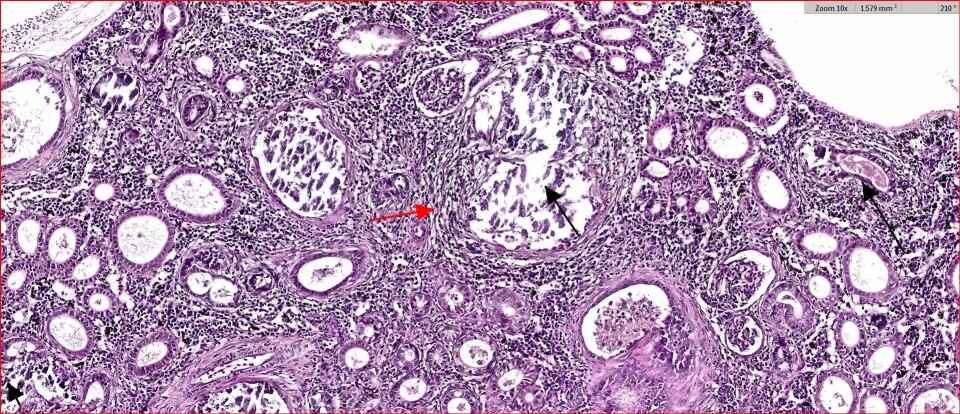

Nefrokalsinose kjennetegnes ved utfelling av kalkholdig materiale i fiskens nyre som kan føre til nyresvikt og nedsatt helse og velferd. Hva det er som gjør at laks får nedsatt nyrefunksjon og hva oppdrettsnæringen kan gjøre for å forhindre sykdommen er lite kjent. Med bakgrunn i det samt at sykdommen er så utbredt så initierte FHF gjennom utlysning i 2019 «Robust laksesmolt i norsk settefiskproduksjon» forskning på problemstillingen.

I tillegg til å vise seg å være svært utbredt i settefiskanleggene i Midt-Norge så har prosjektet også studert årsakssammenhenger. Vannkvalitet viste seg å være den mest betydelige faktor for nefrokalsinose, selv om fôrsammensetning muligens spilte en sekundær rolle. I anleggene som tilsatte sjøvann i løpet av produksjonen fikk en større andel fisk påvist alvorlige grader av nefrokalsinose. De har så langt ikke funnet noen sammenheng mellom nefrokalsinose og HSS (Hemoragisk smolt syndrom) som det har blitt spekulert i tidligere.